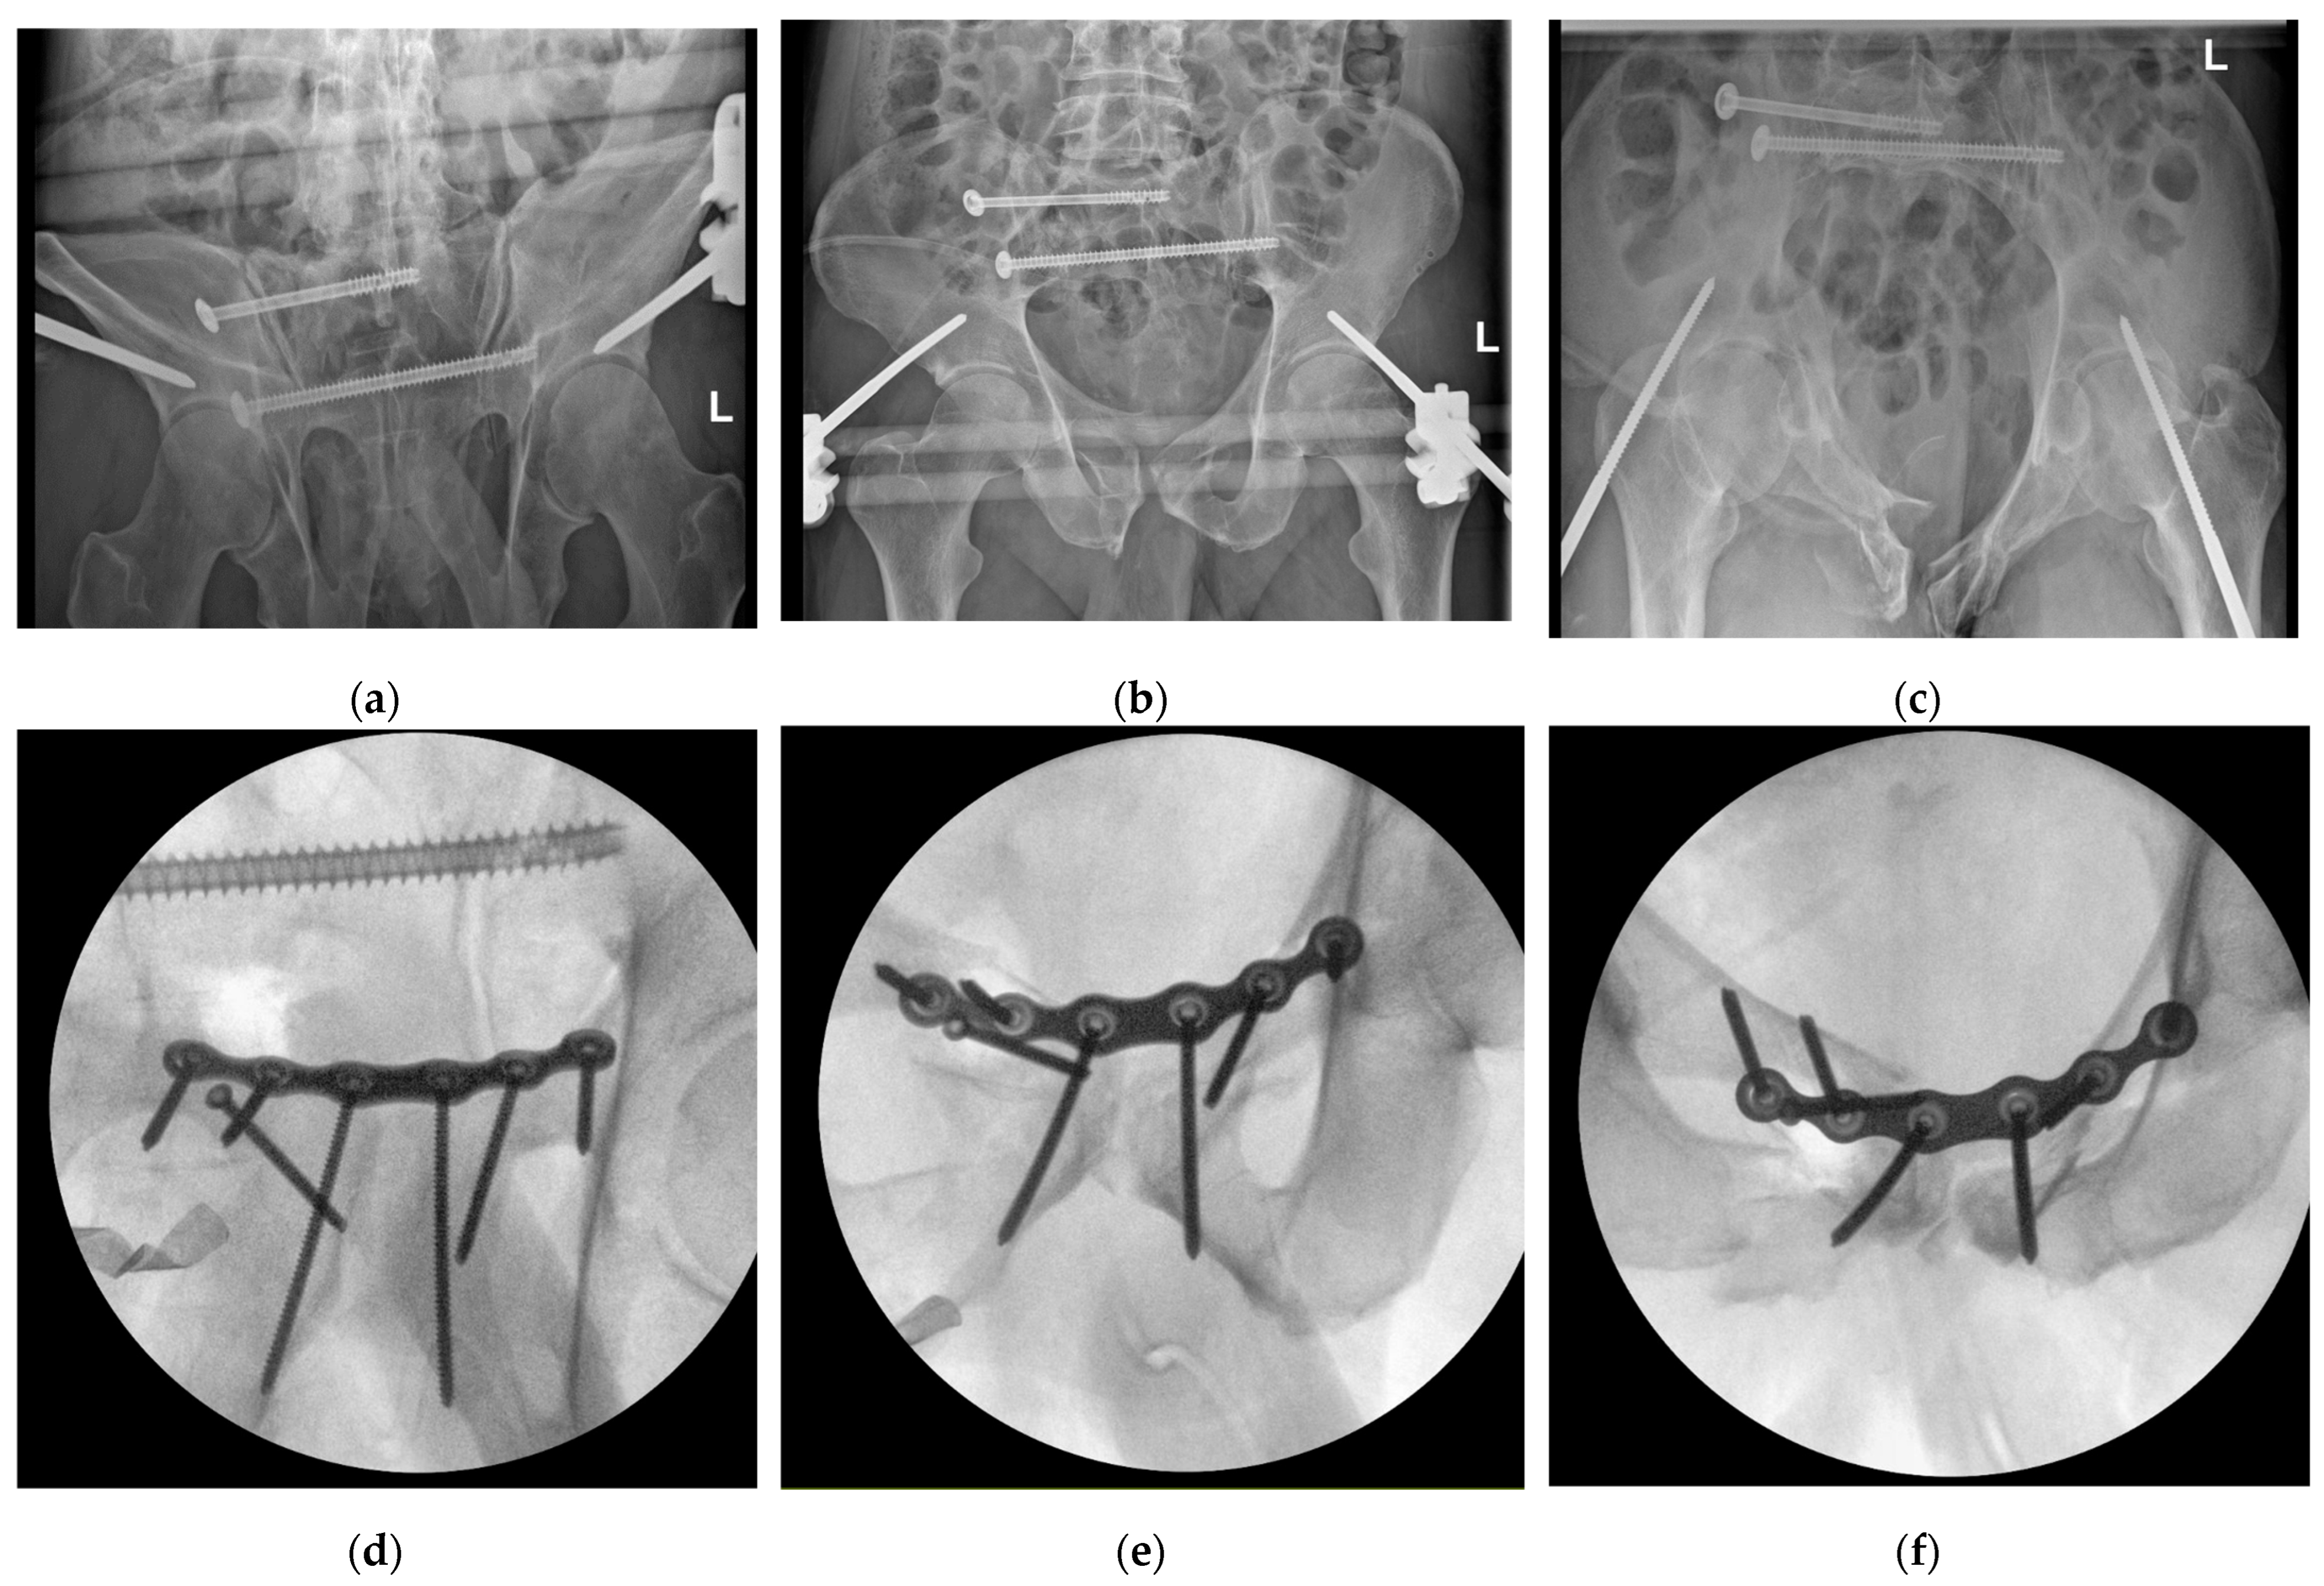

3.5. Fracture Repositioning and Osteosynthesis

3.6. Outcomes